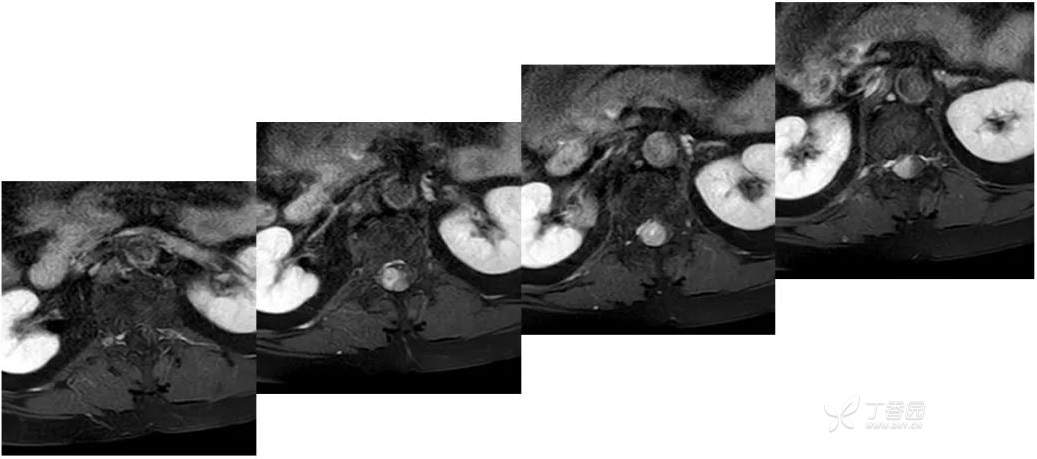

MR: